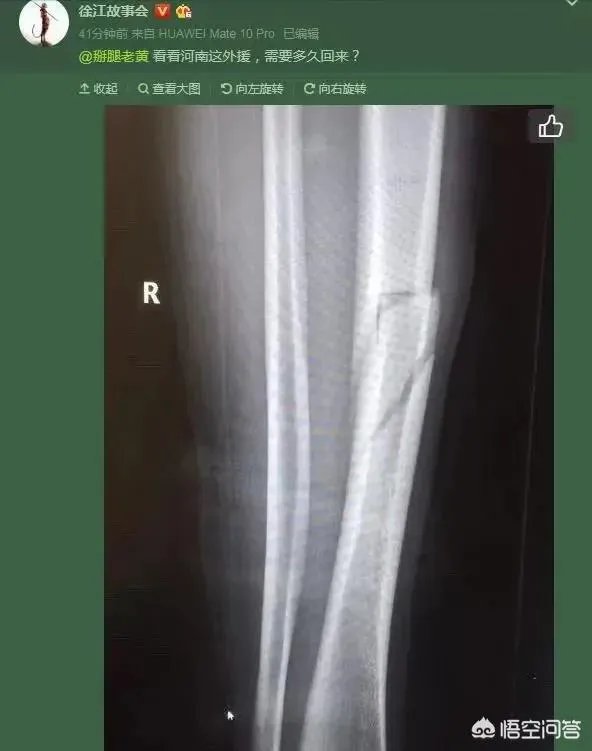

在比赛结束后不久传来的消息让人心情深感沉重,多拉多右腿胫骨骨折,

再之后就是被救担架抬上救护车前往医院,经过检查确认为右腿胫骨骨折,多拉多的中超之旅在刚刚开始之时即吿终结,实在让人为其惋惜感慨。